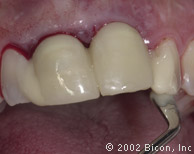

Вид спустя десять недель после установки имплантантов

Установка двух 3.0mm Impression Post

Снятие слепка и подбор цвета